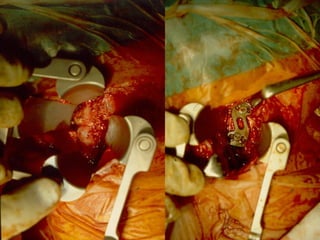

OOppeerraattiivvee mmaannaaggeemmeenntt

 OOppee rraattiivvee

AApppprrooaacchh

–AAnntteerriioorr ddeeccoommpprreessssiioonn // ssttaabbiilliizzaattiioonn

–PPoosstteerriioorr ddeeccoommpprreessssiioonn // ssttaabbiilliizzaattiioonn

–CCoommbbiinneedd

 AAnntteerriioorr ddeeccoommpprreessssiioonn

– TTrraaccttiioonn

– IInnttrraaooppeerraattiivvee ddiissttrraaccttiioonn

– MMiiddlliinnee ttrroouugghh

– BBoonnee//ddiisscc ffrraaggmmeenntt rreemmoovvaall

 GGrraaffttiinngg

– NNoottcchheedd ((nnoo ppllaattee))

– AAllllooggrraafftt –– ffiibbuullaa

– AAuuttooggrraafftt –– iilliiaacc

ccrreesstt

 AAnntteerriioorr ppllaattee

– BBiiccoorrttiiccaall –– uussee

iimmaaggeess,, ppeenneettrraattee

ppoosstteerriioorr ccoorrtteexx

((1mmmm))

– UUnniiccoorrttiiccaall –– lloocckkiinngg

ssccrreeww ssyysstteemm